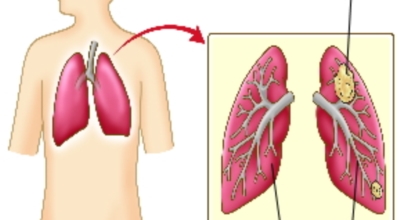

폐암 검사는 X-ray를 통해서 검사하는데 , 크기가 작거나 구석에 위치한 경우 확인이 어려운 경우도 있답니다. 그리고 조직 검사를 통해서 정확한 진단을 하게 되어요. 폐암이 발견되면 종양의 크기나 전이 여부 , 위치에 따라서 수술 여부를 결정하게 됩니다.

수술 치료

악성 종양이 있는 폐의 일부를 절제하는 방법입니다. 초기에는 내시경 기구를 이용하여 수술이 가능하기도 합니다.